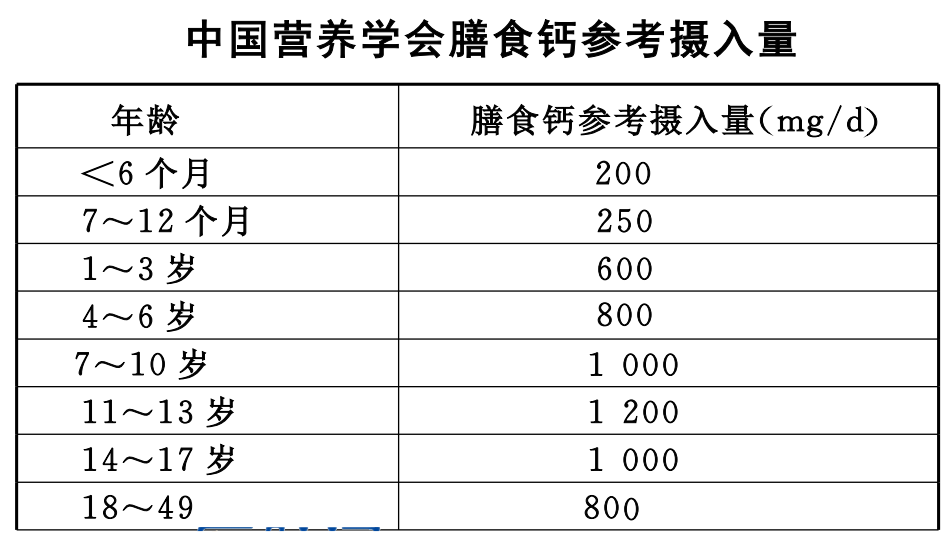

1、均衡营养,适当补钙

保证每日膳食丰富、营养均衡是防治骨质疏松症的基础生活方式。

饮食上应多吃钙和维生素 D 含量较高的食物,如蔬菜、鱼类、蛋类、豆腐、菌菇、燕麦、奶制品等。

按照我国老年人每日需钙量 1000~1200 mg 计算,除每日饮食供给 500~600 mg 外,还应补充钙 500~600 mg/d。

2、维生素 D(骨活化剂)

老年人一般维生素 D 吸收代谢(羟化)功能下降,影响钙的吸收,应适当补充。老年人每日维生素 D 摄取量为 400~800 U。